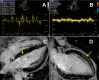

Cardiotoxicity is a rare but serious complication of hydroxychloroquine, a 4-aminoquinoline increasingly used in the treatment of rheumatological disorders. We describe typical clinical, echocardiographic, and histological features of this rare condition according to the currently available literature, illustrated with a recent new biopsy-proven case of hydroxychloroquine cardiotoxicity in a 52-year-old female with rheumatoid arthritis. Presentation in this case was of a rapidly progressive decompensated biventricular cardiomyopathy associated with recurrent biomarker elevations, conduction system disease, and possibly neuromyotoxicity. Death occurred suddenly 2 months after diagnosis despite drug discontinuation and clinical improvement. The potential role of cardiac magnetic resonance delayed gadolinium enhancement imaging in the prognosis of this toxic cardiomyopathy is also introduced. This case-based literature review highlights that, although rare, hydroxychloroquine cardiotoxicity can be fatal, particularly if irreversible histopathological changes have occurred prior to drug discontinuation. Given this, regular screening with 12-lead electrocardiography and transthoracic echocardiography to detect conduction system disease and/or biventricular morphological or functional changes should be considered in hydroxychloroquine-treated patients in addition to recommended ophthalmological screening.